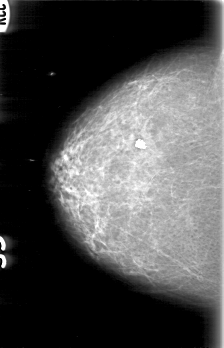

D_4089_1.LEFT_MLO

RIGHT_MLO LINES 5191 PIXELS_PER_LINE 3481 BITS_PER_PIXEL 12 RESOLUTION 43.5 NON_OVERLAY